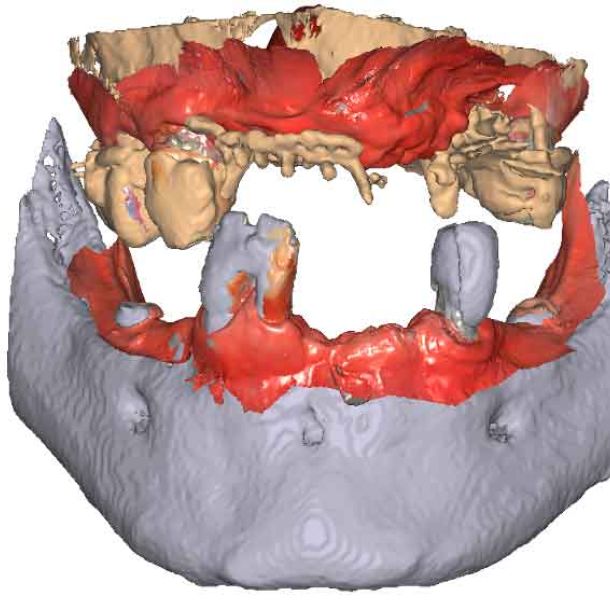

3D models - Bite scan from intra-oral scanner

Step 2 – CBCT acquisition

When traditional IOS scans lack necessary references, Cone Beam Computed Tomography (CBCT) data serves as a possible alternative. By utilizing CBCT scans, clinicians can establish accurate reference positions for treatment planning.

To be able to use CBCT data as initial models, we need to transform the DICOM file into an STL file.